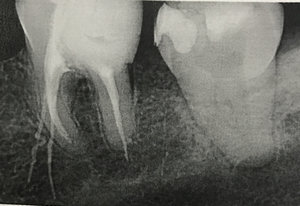

Пожалуйста, подскажите, в чем может быть причина и как её обнаружить? Фото последнего рентгена после установки временной пломбы прилагаю.

Тут все очевидно. Во-первых, у Вас периодонтит (хроническое воспаление), а доктор лечил просто воспаление нерва. А во-вторых, произошел вывод инородного тела за верхушку зуба, что крайне недопустимо.